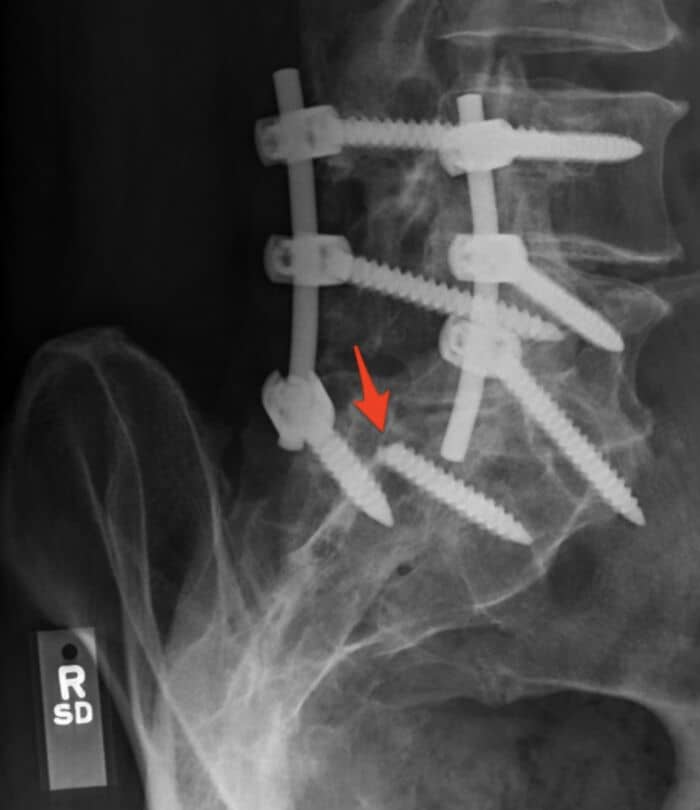

#4 One Of The Screws Holding My Spine In Place Snapped

I had a L4-L5 / L5-S1 spinal fusion. I was sitting at my desk when I felt (and heard) a huge snap in my back. Almost immediately I couldn’t feel or move my left leg.

Turns out that one of the screws snapped. My surgeon was able to add another s***w but had to leave the broken piece in there. 0 out 10 stars – would not recommend.